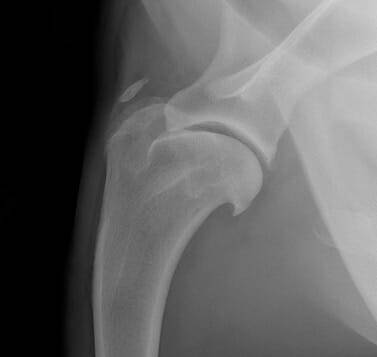

La radiographie simple peut être utile pour évaluer la présence d'une tuméfaction focale des tissus mous et la radiographie "sous contrainte" peut être utile pour documenter l'instabilité de l'articulation en cas de lésion ligamentaire importante ( Figure 2).

La douleur associée à l'insertion du tendon sus-épineux (le plus souvent à la jonction musculo-tendineuse) est une cause fréquente de boiterie non diagnostiquée du membre thoracique, en particulier chez les chiens sportifs. Comme pour les lésions de l'iliopsoas dans le membre pelvien, la boiterie est souvent insensible au repos et aux AINS et s'aggrave après un exercice intense. Le supra-épineux prend naissance dans la fosse supra-épineuse de l'omoplate et s'insère sur le tubercule supérieur de l'humérus. Il produit l'extension de l'épaule et l'avancement du membre et on pense que les lésions sont dues à des blessures répétitives. On l'observe fréquemment chez les chiens de flyball qui frappent de façon répétée la boîte avec un membre tendu. Les chiens cliniquement atteints présentent généralement une gêne à la palpation digitale ferme du tubercule supérieur au niveau du site de la lésion, l'épaule étant maintenue en flexion. La radiographie et la tomodensitométrie peuvent révéler une minéralisation dans le tendon (Figure 5) ; cependant, cette minéralisation est souvent accessoire et ne provoque généralement la douleur qu'en provoquant un conflit avec le tendon d'insertion adjacent du muscle biceps (Figure 6).